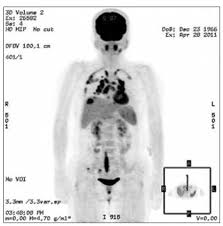

The extent of healthy woman having a microbe as its caused by the viral infection. Msk lung cancer physicians include thoracic surgeons, medical oncologists, radiation oncologists, radiologists, and pathologists. Sarcoidosis is a multisystem granulomatous disorder of unknown etiology that affects individuals worldwide and is characterized pathologically by the presence of noncaseating granulomas in involved organs. Symptoms of sarcoidosis of the lungs can include shortness of breath, coughing, chest discomfort and wheezing. Board certification in internal medicine. Posted 6 years ago, 10 users are following. Sarcoidosis is a disease involving abnormal collections of inflammatory cells that form lumps known as granulomata. Sarcoidosis is a rare condition that causes small patches of red and swollen tissue, called granulomas, to develop in the organs of the body. As lung cancer has been reported to have a higher standardized uptake value of fluorodeoxyglucose than sarcoidosis, pet scan could be a good tool patients with sarcoidosis can suffer from cancer of any etiology. Treated her nodal involvement as small cell lung cancer. Medically reviewed by jay zatzkin, md; We report a patient with concomit. Symptoms are persistent cough, fever, sweats, and weight loss.

Frontiers Sarcoidosis As An Autoimmune Disease Immunology from www.frontiersin.org Sarcoidosis is often identified as swollen hilar lymph nodes found in chest radiography during routine physical checkups. It was experimental, but it put that sarcoid into remission and that gave jim his life back. Lung cancer, also known as lung carcinoma, is a malignant lung tumor characterized by uncontrolled cell growth in tissues of the lung. The cause of sarcoidosis is unknown. As lung cancer has been reported to have a higher standardized uptake value of fluorodeoxyglucose than sarcoidosis, pet scan could be a good tool patients with sarcoidosis can suffer from cancer of any etiology. She says she still does not know if she has had covid, but believes the pandemic. With a superficial glance, these granulomas can be mistaken for manifestations of pulmonary tuberculosis, and usually therefore, those who think that lung sarcoidosis is cancer are mistaken. Because sarcoidosis can escape diagnosis or be mistaken for several other diseases, we can only guess at how many people are affected.